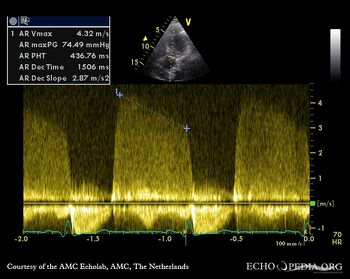

E00422.jpg

Continuous-wave signal of moderate aortic regurgitation